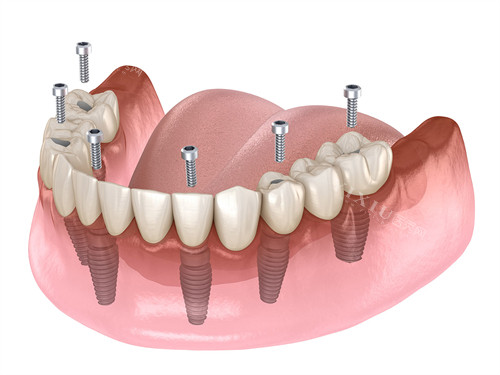

种植修复类

瑞士ITI亲水种植牙:8128元起

全口义齿修复:20912元起